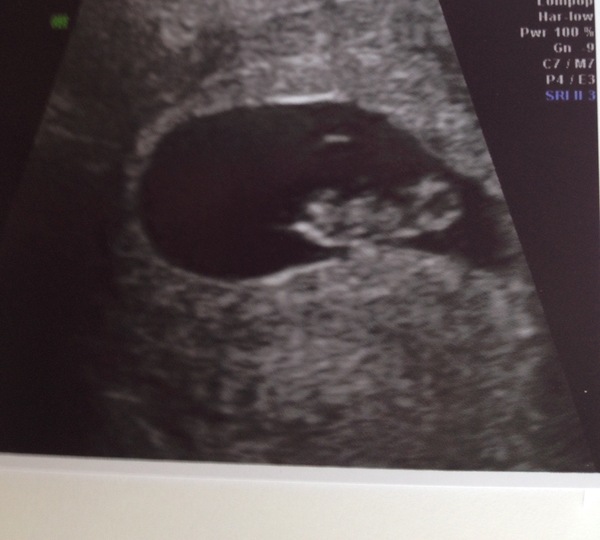

Had my scan yesterday which measured 7+6 exactly as I thought (15mm) and I was overjoyed to see the heartbeat. How I wish the nhs scan would project the picture on the wall in front of the bed like that. A 12 week scan would be mind-blowing!

Lovely scan pic Krissy, glad it went well 🙂

Lovely scan pic by the way Krissy Smile sorry I didn't comment sooner, I saw it when I was half-awake this morning haha.